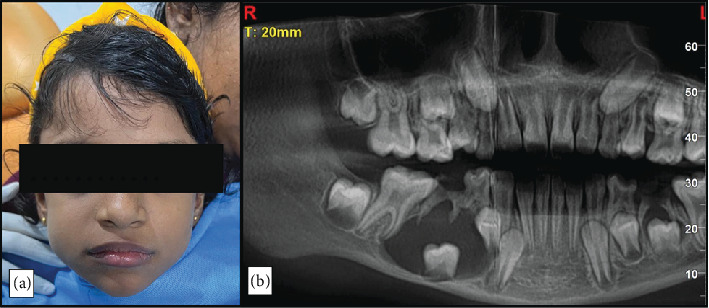

牙源性囊肿(dc)是一种牙源性囊肿,通常与未出牙或阻生牙的牙冠有关,通常在牙长得很大或感染时发现。虽然在成人中很常见,但在儿童中很少发生。大多数儿童病例是在常规乳牙感染x线检查中偶然发现的。治疗方法因病变的大小和范围而异,剜出和有袋化是常用的方法。尽管技术不同,总体预后和治疗结果通常是有利的。本病例报告描述了一名8岁女性通过有袋化结合定制丙烯酸闭孔成功保守治疗下颌骨DC。

Dentigerous cysts (DCs) are odontogenic cysts typically associated with the crowns of unerupted or impacted teeth and are usually discovered when they reach large sizes or get infected. Although common in adults, their occurrence in children are rare. Most cases in children are incidentally discovered on routine radiographic examination of infected deciduous molars. Treatment methods vary based on the size and extend of the lesion, with enucleation and marsupialization being the commonly employed approaches. Despite the variation in techniques, the overall prognosis and treatment outcomes are generally favorable. This case report describes the successful conservative management of a mandibular DC in an 8-year-old female through marsupialization in conjunction with a custom-made acrylic obturator.